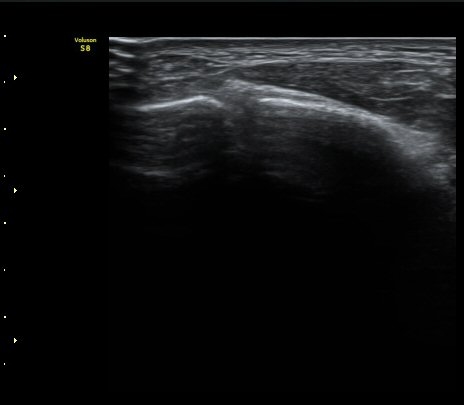

Á¾°ñÀÔ¹æ°ñÀδëÀÇ Á¾´Ü¸é°Ë»ç¿¡¼­ ÀδëÀÇ Á¾°ñ ºÎÂøºÎ ÆÄ¿­ÀÌ °üÂûµÊ(»çÁø 1, 2, 3).